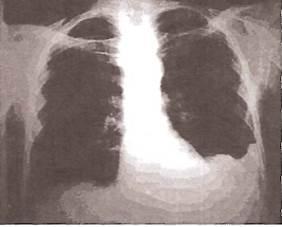

При выпотном плеврите

наиболее ранним рентгенологическим признаком скопления жидкости в плевральной полости является сглаживание (облитерация) острого реберно-диафрагмального угла с вогнутой верхней границей уровня жидкости (R.H. Ingram, 1995; рис. 22).

Рис. 22

. Сглаживание острого реберно-диафрагмального угла при небольшом объеме плеврального выпота.

По мере нарастания объема экссудата на рентгенограммах начинает определяться однородное затемнение, которое прилежит к наружному краю грудной клетки и диафрагме. Верхняя граница затемнения чаще располагается косо — сверху вниз и снаружи кнутри (рис. 23). При перемене положения тела затемнение и его верхняя граница меняют свою форму и расположение в связи с перемещением жидкости (рис. 24).